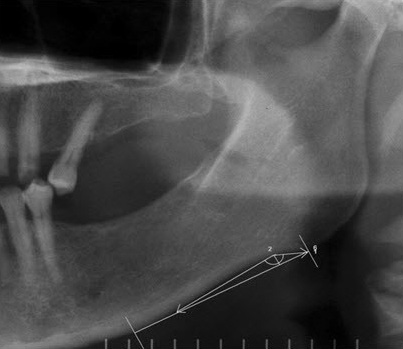

– antegonial angle: 2 lines are drawn tangent to the edge of the inferior border of the mandible that intersect each other at the deepest part of the antegonial notch. The angle between these 2 intersecting lines is referred to as the antegonial angle (Figure 2)19;

– antegonial notch depth: the distance of a perpendicular line from the deepest point of the antegonial notch concavity to a line tangent to the inferior border of the mandible (Figure 2, Figure 3, Figure 4)19;